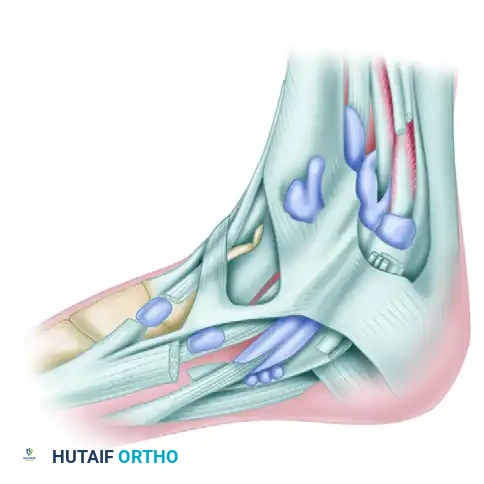

Figure 82-40: Bursa beneath the insertion of the anterior tibial tendon.

- Beneath the Inferior Extensor Retinaculum: The second common site of rupture is beneath the superomedial limb of the inferior extensor retinaculum. As this limb of the retinaculum reaches the anterior tibial tendon from its lateral side, it divides into an anterior and posterior "glove," completely encircling the tendon as it passes toward its insertion on the medial midfoot.

Figure 82-41: Numbers 3 and 4 point to the superior and inferior subdivisions of the superomedial band of the inferior extensor retinaculum. This split envelops the tendon. 1, Stem of inferior extensor retinaculum; 2, anterior tibial tendon; 5, inferior limb of inferior extensor retinaculum.

Figure 82-42: 1, Sheath of anterior tibial tendon; 2, sheath of extensor digitorum longus; 3, sheath of extensor hallucis longus; 4, inferior extensor retinaculum; 5, superomedial arm of inferior extensor retinaculum; 6, inferomedial arm of inferior extensor retinaculum.